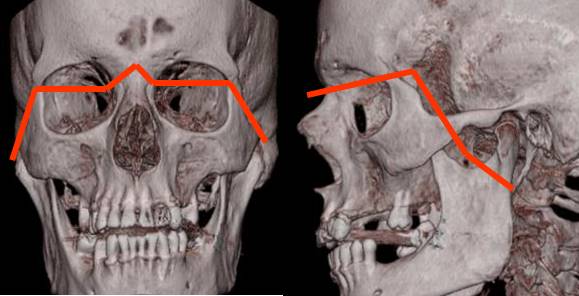

Fig 225. Diagrama de Lefort III.

Fractura donde se separa la cara del cráneo. Compromete la sutura nasofrontal, borde interno y externo de la órbita y el arco cigomático.

Fig 226. Lefort III.

A: TAC axial y B: TAC reconstrucción coronal. Múltiples fracturas en los antros maxilares y los rebordes orbitarios. En el lado derecho hay compromiso del piso de la órbita y el arco cigomático. (Flecha gruesa).

Fig 227. Lefort III.

A: Rx lateral, B: TAC axial y C: TAC reconstrucción coronal. Severo estallido facial con fracturas deprimidas de la parte anterior de la cara y Lefort III bilateral.